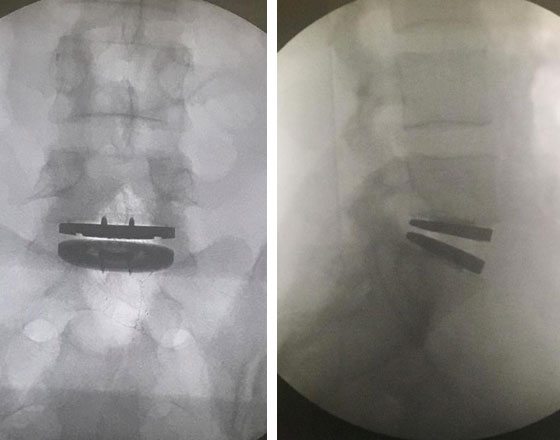

Prótese de disco

Artrodese

Lombar